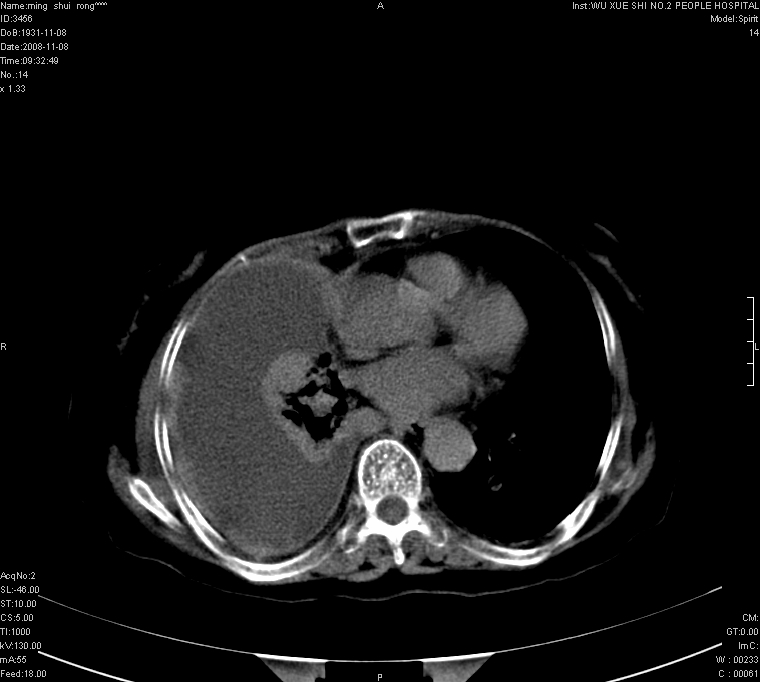

75.女.胸痛

75.女.胸痛 。右侧胸廓稍塌陷,右侧胸膜广泛增厚,并见多发结节及肿块影,右侧大量胸腔积液,纵隔固定无移位;首先考虑恶性病变,胸膜间皮瘤可能性大。

75.女.胸痛 。右侧胸廓稍塌陷,右侧胸膜广泛不规整增厚,并见部分肺组织实变,右侧大量包裹性胸腔积液,纵隔固定无移位;1.考虑结核性。  2,考虑胸膜间皮瘤可能性大。(建议胸水检查)

右侧胸腔可见弧形低密影,右侧胸膜广泛不规则增厚,右肺不张,纵隔右移。考虑:右侧恶性胸膜间皮瘤可能大,请结合临床。

75.女.胸痛 。右侧胸廓稍塌陷,右侧胸膜广泛增厚,并见多发结节及肿块影,右侧大量胸腔积液,纵隔固定无移位;首先考虑恶性病变,胸膜间皮瘤可能性大或肺癌胸膜转移。

右侧胸膜广泛增厚,并见多发结节及肿块影。右侧大量胸腔积液。考虑1.恶性胸膜间质瘤?2.胸膜转移瘤?建议胸水检查。